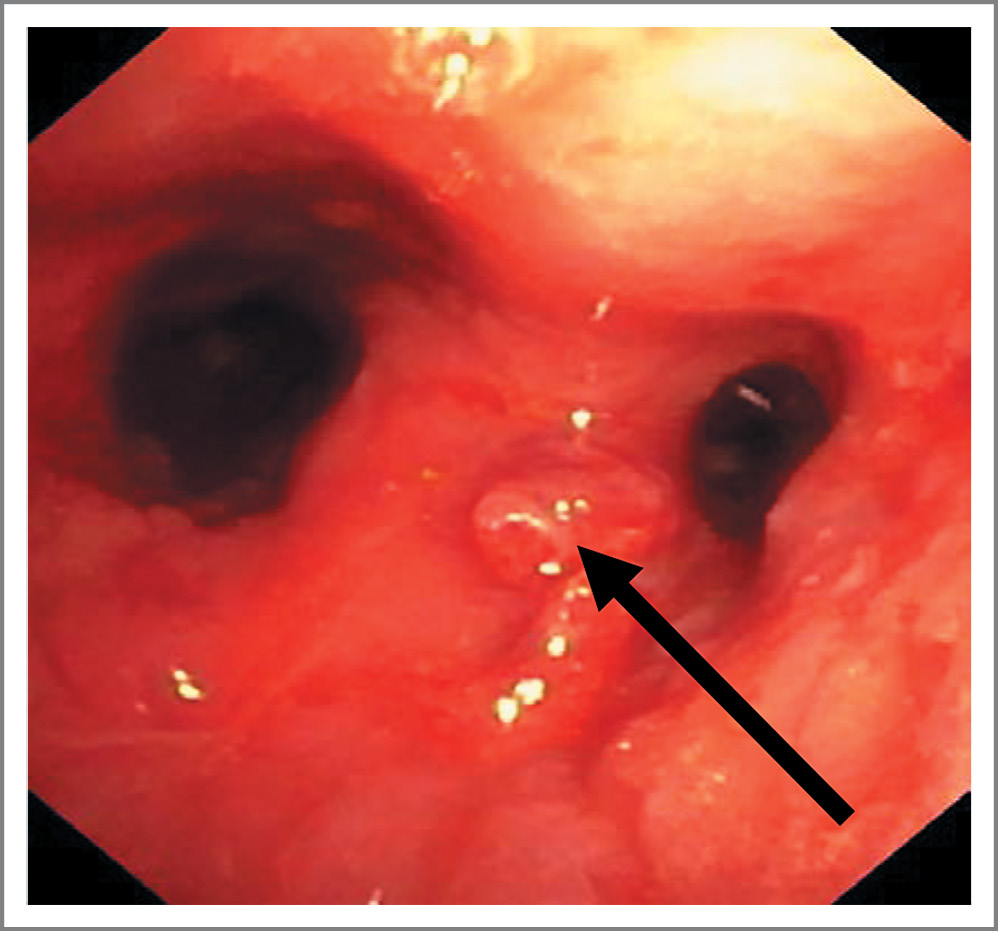

При ларингоскопии выявлено циркулярное сужение просвета подскладочного пространства гортани и трахеи (до 6–7 мм) рубцовой тканью, в связи с чем было невозможно провести бронхоскоп через рот. При бронхоскопии (через трахеостому) на передней стенке гортани визуализировано полиповидное образование высотой 0,3 см и диаметром 0,2 см. Стенки трахеи и крупных бронхов мелкобугристые (плюс-ткань), слизистая утолщена и контактно кровоточива, с множественными грануляциями, суживающими просвет главных бронхов и промежуточного бронха справа (рис. 1).

Рис. 1. Бронхоскопия. Стенки трахеи и крупных бронхов мелкобугристые (определяется плюс-ткань), слизистая с множественными грануляциями, суживающими просвет главных бронхов.

Fig. 1. Bronchoscopy. The walls of the trachea and large bronchi are finely lumpy (plus tissue is determined), mucous with multiple granulations narrowing the lumen of the main bronchi.